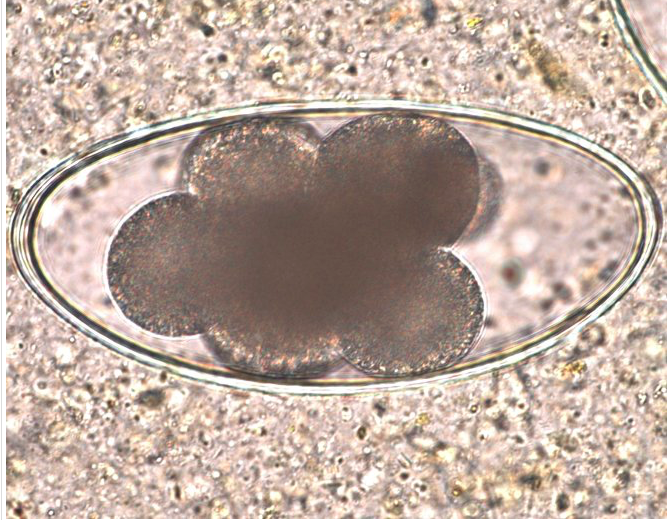

Infection of foals with the parasite whose egg is shown in the image below can be prevented by which of the following? The microscopic image was taken at 40X; the egg is approximately 50 um.

This image shows a Strongyloides westeri egg. Strongyloides pass from the host in the larvated form and are recognizable as an oval-shaped, thin-shelled embryonated egg.

Larvae of Strongyloides westeri are transmitted to foals in the mare’s milk. Adult horses rarely have patent infections except when larvae harbored in their tissues migrate into a mare’s milk after parturition. The worms are found in the small intestine and may cause diarrhea in young horses. Ivermectin or oxibendazole are effective in treatment of S. westeri.